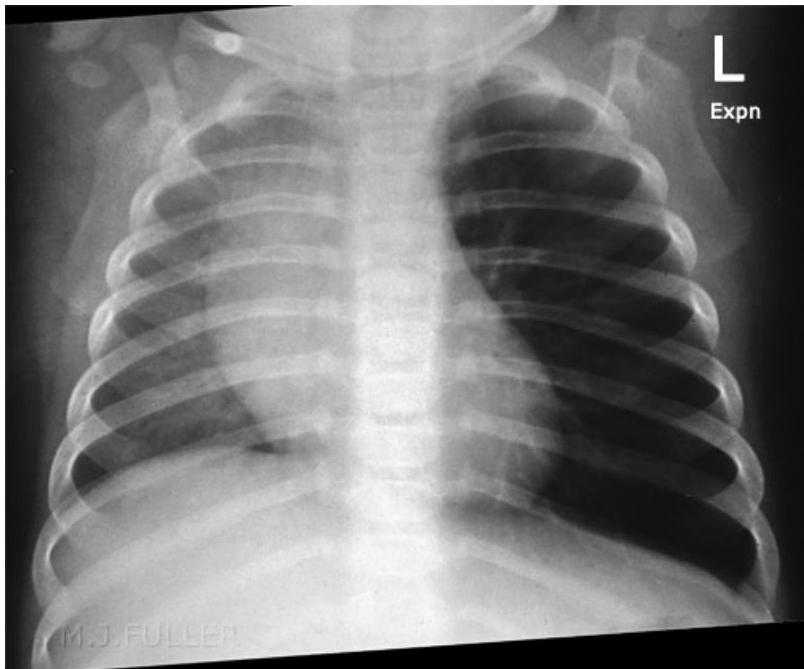

- Expiratory Chest X-ray or Fluoroscopy:

- Indicated for children with a suggestive presentation but normal inspiratory X-ray.

Radiological Findings:

- On Inspiration: Lungs may appear similar as airways widen, allowing air past the FB.

- On Expiration: The FB can obstruct the bronchus as its diameter decreases. The greatest difference in lung aeration is seen here, as air is trapped in the affected lung while exhaled from the normal lung.